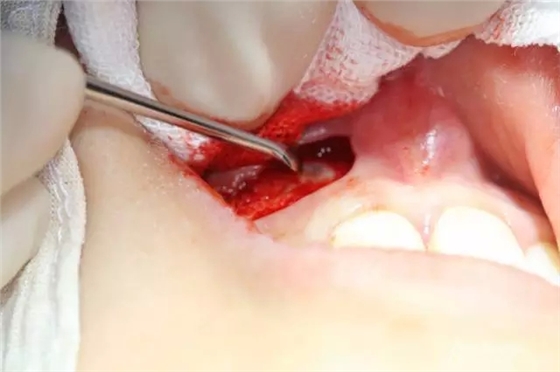

病例資料: 患者、柴xx、女、16歲。??茩z查及病歷如下圖: 患者同意我院正畸科建議,遂轉(zhuǎn)診倒外科。術(shù)前簽知情同意書。 治療過程: 圖1.術(shù)前的CBCT檢查:13阻生,疑為含牙囊腫。縱剖面顯示12牙根吸收至根尖1/3。 圖2.局部麻醉下 。行唇側(cè)弧形切口,12松動不到1°。 圖3.翻瓣、暴露骨面。 圖4.去骨、 暴露13牙冠 圖5.去骨、逐漸顯露13。 圖7.拔除13. 圖8.摘除囊壁 圖9.必須完整剝離囊壁。 圖10.摘除囊壁后形成的骨腔 圖11.超聲骨刀12根尖倒預(yù)備 圖13. 消毒棉球骨腔內(nèi)隔濕血液,紙尖干燥倒預(yù)備好的根管 圖14. 紙尖無血即可 圖15。MTA倒充填 圖16.骨腔填塞膠原蛋白海綿 圖17.拔除的13及摘除的囊壁 圖18.縫合 圖19.術(shù)后x線根尖片影像:MTA封閉根尖